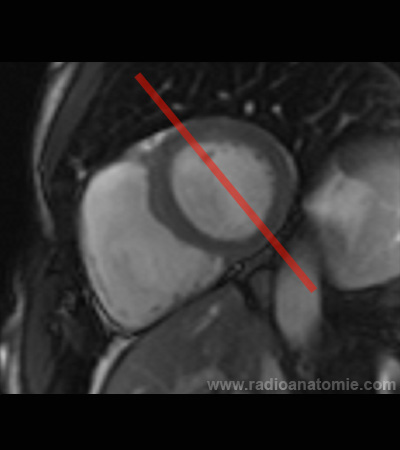

Radioanatomie et plans de coupe en IRM cardiaque

Plan 4 cavités

Plan 2 cavités

Plan chambre de chasse du ventricule gauche (LVOT)